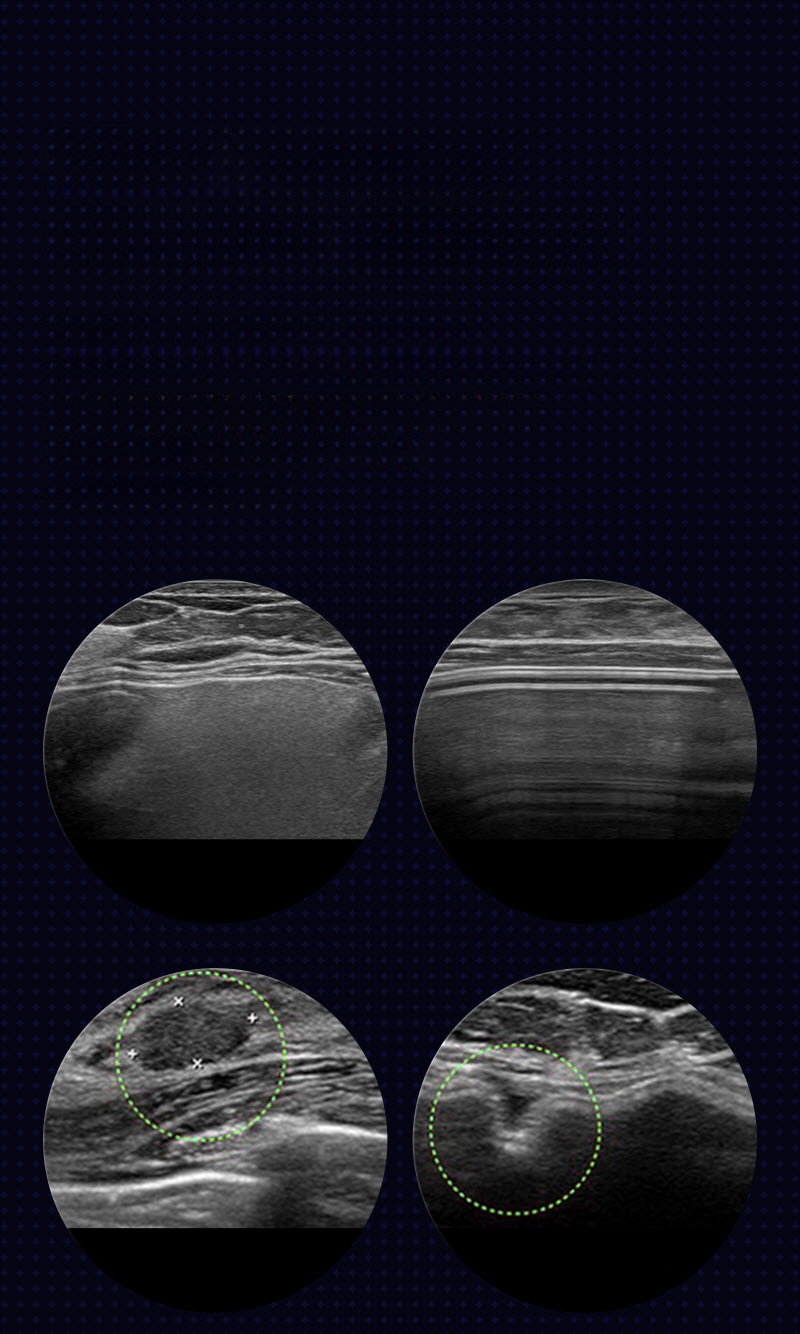

We establish a surgical plan after checking the position of the implant, rupture, capsular contracture, capsule thickness, and cause of edema through ultrasound examination.

We perform revision surgery to improve issues such as capsular contracture, breast asymmetry, implant rupture, dissatisfaction with shape, and rippling.